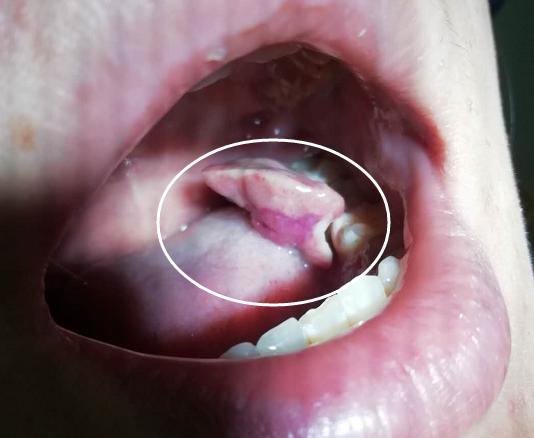

“左下边,大牙根部不知道什么时候肿了起来,慢慢长成了一个小肉瘤。吃饭时常常不小心咬出血。”小晓告诉徐晓欣主任,“以前也看过,医生说这是怀孕后激素变化,导致牙龈慢性炎症加重,生完孩子后可以自行减轻或消退。”就这样忍了四个月,终熬到了生产,然而“生完孩子后我每天都在观察,发现‘瘤子’依旧那么大,没有减小的迹象。”数着日子忍到出月子,她就赶紧来口腔科请医生“排雷”。

仔细询问情况后,徐主任为小晓做了口腔检查:“患者口内发现大小约2cm的妊娠期牙龈瘤,蒂在左下第一磨牙和第二磨牙间舌侧牙龈乳头处。”在徐主任的建议下,小晓先进行了牙周基础治疗,去除引起牙龈炎症的罪魁祸首——牙菌斑,使龈瘤体积缩小,再接受牙周手术,切除困扰她近半年的牙龈瘤。